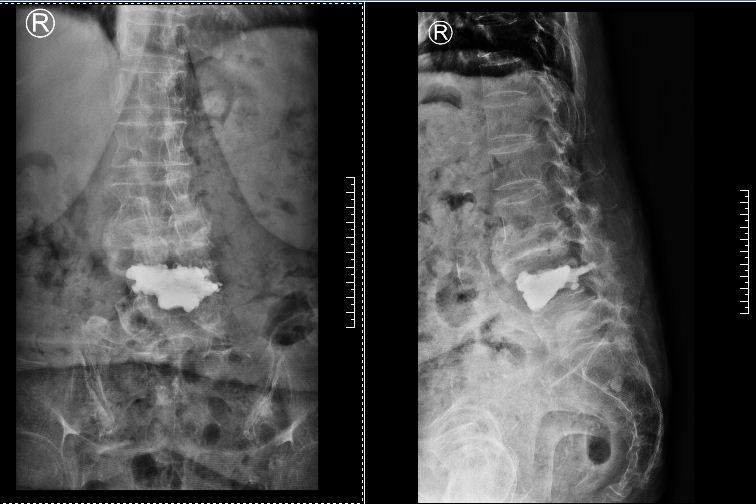

歷經三個半小時,手術順利完成。術后當晚,張奶奶就表示,腰疼明顯好多了,可以獨自翻身,腿也靈活了。

▲術后磁共振、X片

經過進一步康復治療,又過了兩天,張奶奶已經可以獨自下地走路了,如同重獲新生。她對曾小軍的技術贊不絕口,對醫(yī)護人員的照顧感激不盡。